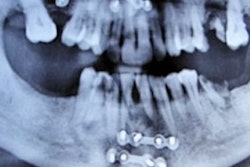

The man was referred to an oral surgeon to have an impacted tooth treated after experiencing intense swelling and pain. An orthopantomogram of the patient showed both jaws with normal teeth. Horizontally impacted mandibular third molars were seen. A linear radiopacity was detected, extending coronally between teeth #44 and #45 and extending apically below the roots of tooth #46, resembling an impacted supernumerary tooth, according to the authors.

Ultrasonography was performed for better imaging of the soft-tissue swelling. Upon closer review, the clinician was able to see that the patient had a 2-cm-long sialolith instead of an impacted tooth, the authors wrote.

Misinterpreting the finding of a linear radiopacity mimicking an impacted tooth on an orthopantomogram is highly unusual. To differentiate between a sialolith and an impacted tooth on orthopantomogram, clinicians should look for a lack of sclerotic margins of lamina dura, absence of radiolucent central pulp chamber, and differential radiolucency between enamel and dentin. Clinicians also should consider using other types of diagnostic tools, the authors wrote.